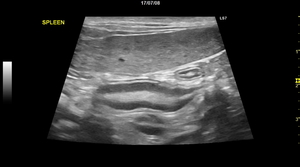

↑Examine the condition of the heat muscle, red indicates muscle contraction and blue indicates muscle expansion.  By measuring E/e ratio, it is possible to diagnose the systolic dysfunction and diastolic dysfunction of the heart. This image examines left atrial pressure, risk of pulmonary edema, left ventricular diastolic and systolic function  The movement of each part of the heart wall (myocardium) is measured, to check the condition of the heart ◆ABDOMINAL ORGANS ・Liver (liver cancer) ・Stomach     ・Spleen ・Intestines     ・Bladder (cystitis, stones) ・Kidney     ・Prostate (prostate hypertrophy) ・Uterus (uterine edema)     ・Gall bladder (cholelithiasis) ・Gall bladder (gall bladder rupture)     ・Adrenal gland ・Pancreas (pancreatitis)     ◆EYES ★uses a special eye examination probe ・Cataract ・Vitreous inflammation     ・Retinal detachment   ……etc. |